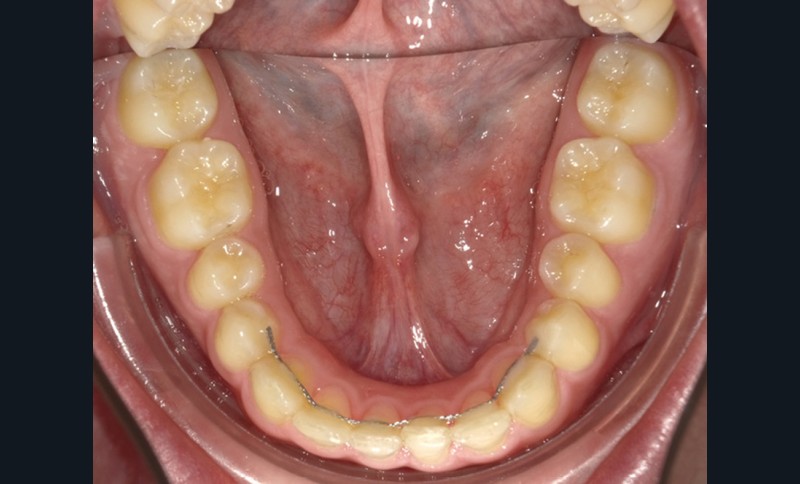

C’est à ces questions que nous permettront de répondre les deux premiers conférenciers, parodontologistes : le Dr Béatrice Straub nous présentera le renfort parodontal minéralisé, technique qu’elle a développée et pratique depuis de nombreuses années, pour éviter les préjudices des mouvements orthodontiques à risque, notamment lors des décompensations préchirurgicales (fig. 1a-d) ; le Pr Anton Sculean abordera le thème des greffes, avec leurs indications, les différentes techniques à privilégier et illustrera ses propos par de nombreux cas cliniques aux résultats esthétiques impressionnants.

Le Dr Christophe Dunglas développera ensuite l’intérêt du cone beam lors de la mise en place des canines incluses difficiles. En effet, la préparation d’ancrages adéquats et de gestes chirurgicaux a minima préviendra l’apparition de résorptions radiculaires et de lésions parodontales.